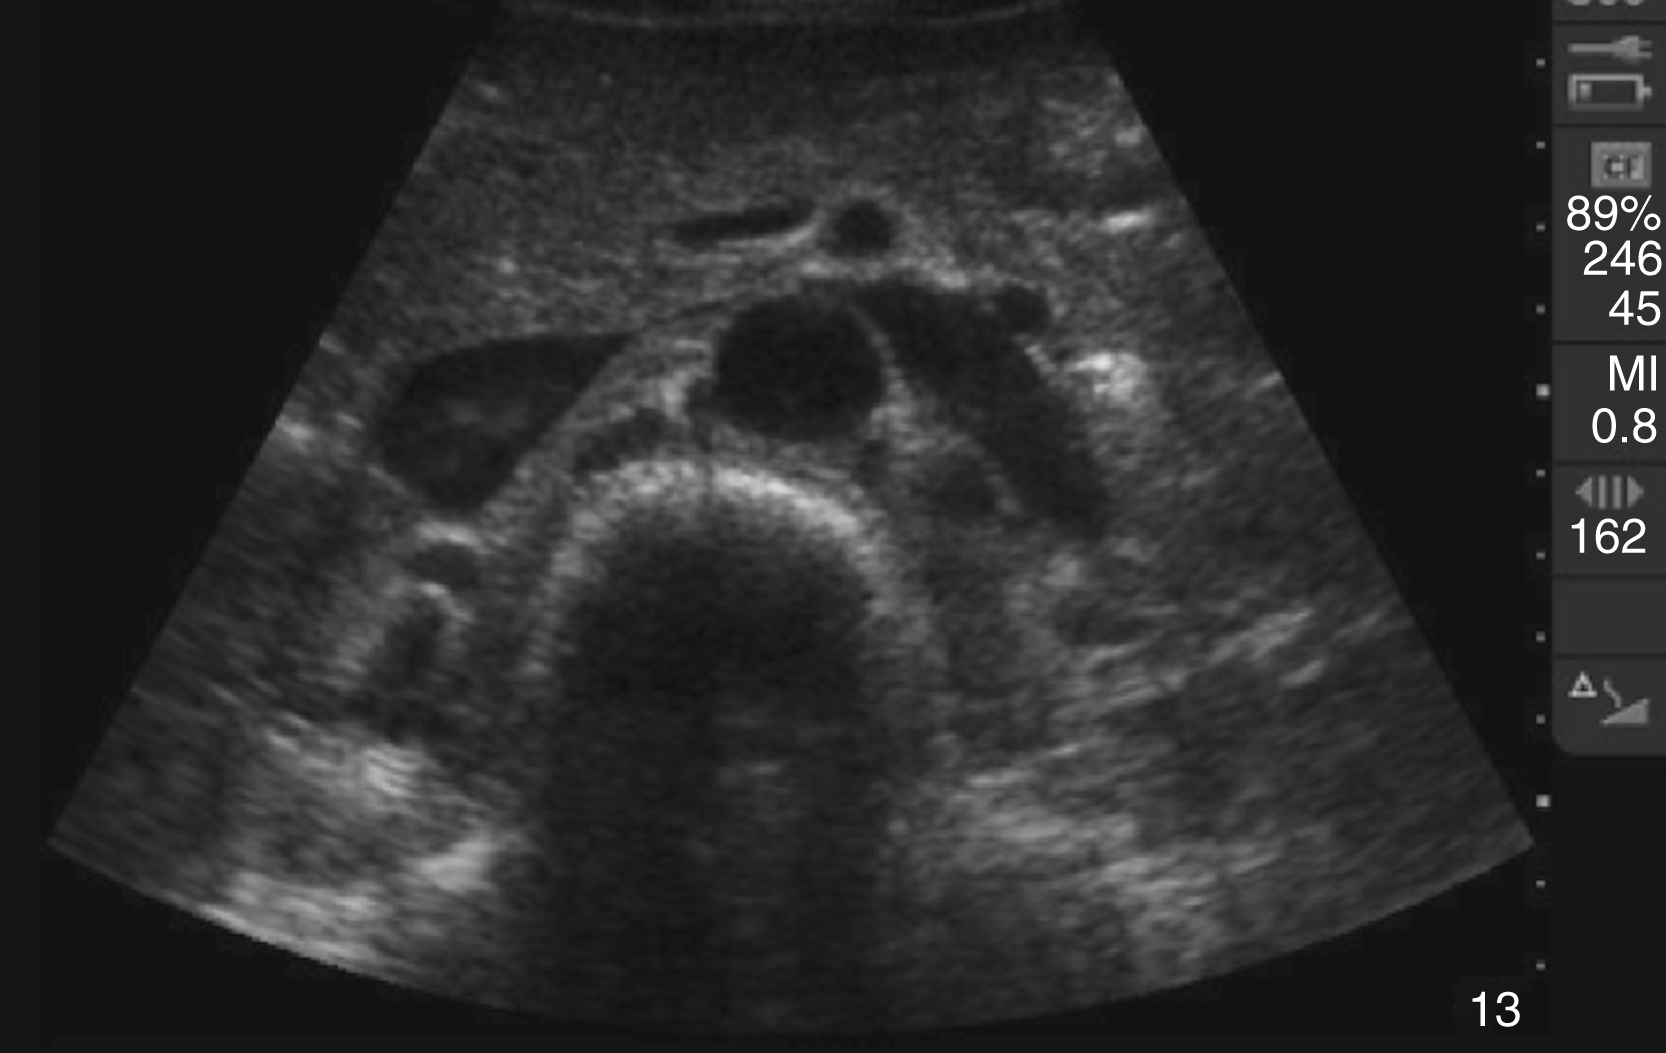

Pathology

Pericardial fluid is typically anechoic, although it can contain internal echoes in cases of pericardial hemorrhage or infection. Large pericardial effusions are usually circumferential but can be loculated. As a result, assessment for pericardial effusion should include multiple views, when feasible, to confirm diagnosis and to avoid mistaking the epicardial fat pad for a pericardial effusion. Although cardiac tamponade is a clinical diagnosis, there are several suggestive echocardiographic features, including diastolic collapse of the RV ( Video e3.9 ), loss of respiratory variation of the IVC ( Fig. e3.11 ), and transvalvular flow velocity paradoxus.

Fig. e3.11

Plethoric IVC showing where to take a measurement.